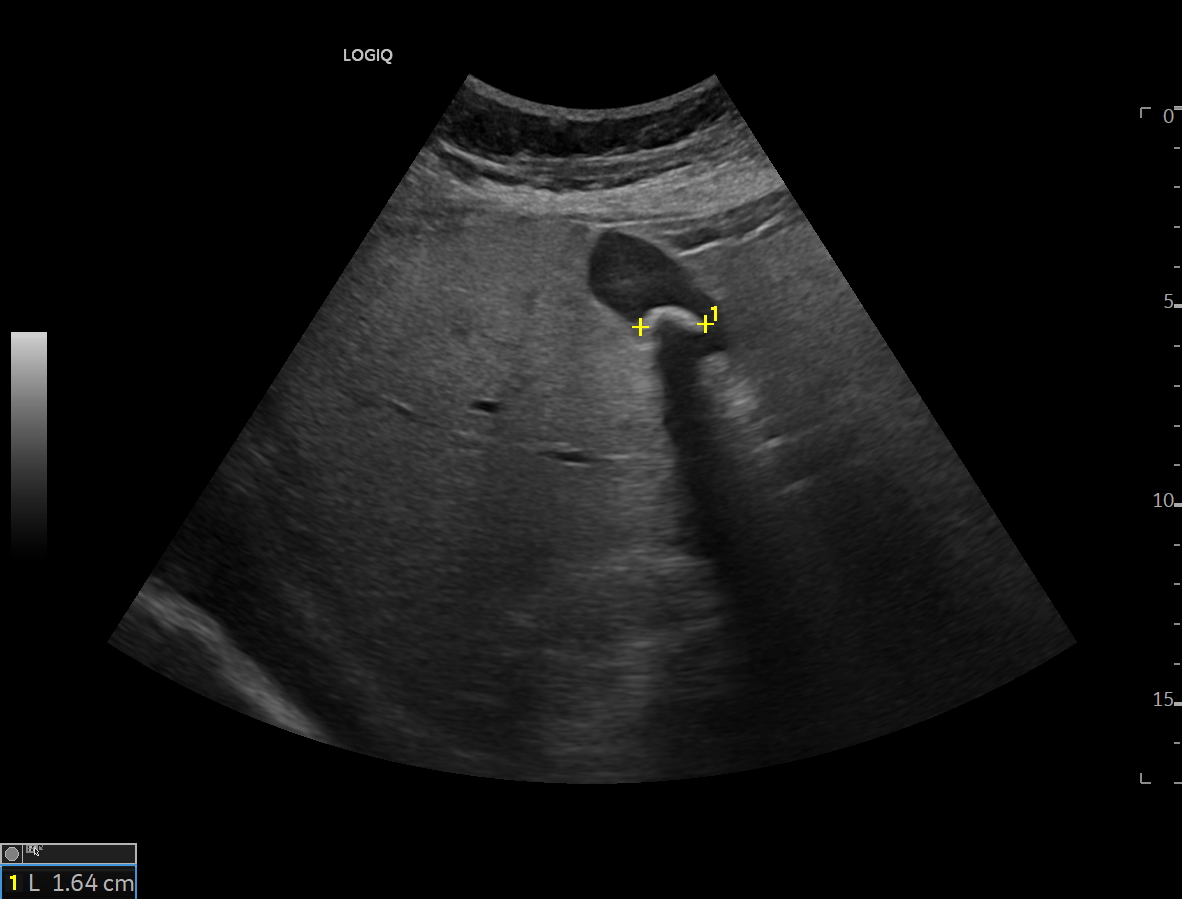

Se realiza ecografía clínica objetivando esteatosis hepática así como litiasis en vesícula biliar que mide 1,6 cm sin signos de complicación. A nivel del riñón derecho presenta lesión hiperdensa en zona media y polo inferior que no capta con realce, sin apreciarse dilatación de cáliz. Se consulta con radiólogo de guardia que indica realizar TAC abdominal para filiar.